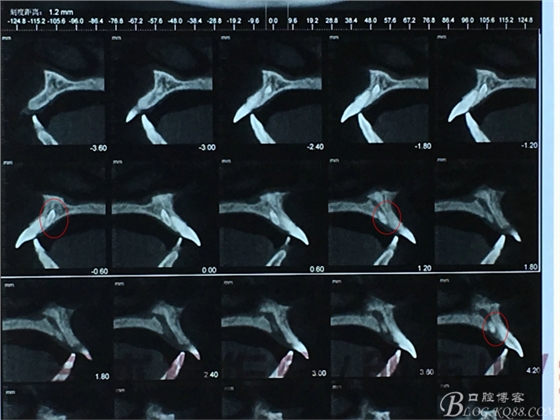

患者、張xx、女、24歲。主訴:上前牙前突伴散在牙間隙,要求正畸治療。??茩z查:11、21唇側(cè)傾斜。中度超合。全景片檢查:11和21根尖區(qū)有兩枚導(dǎo)致多生牙。CBCT檢查:左側(cè)導(dǎo)致多生牙部分牙體位于鼻腭管內(nèi),且位置位于21根尖區(qū)。遂轉(zhuǎn)外科會(huì)診拔除兩枚多生牙。而后再做正畸治療方案 。外科檢查:腭側(cè)未捫及明顯隆起,僅通過CBCT檢查:兩枚多生牙位于11和21根尖區(qū)。術(shù)前同患者充分溝通,說明有損傷鼻腭神經(jīng)及11和21牙根的可能性?;颊吆炛橥鈺?。

圖4.CBCT檢查:21根尖區(qū)的多生牙位于鼻腭管內(nèi)